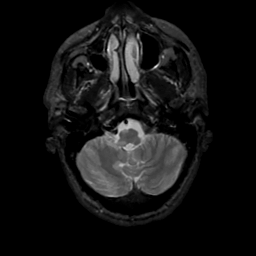

MR Study #4, March 3, 1991 -- Slice #8

[Home][Help][Clinical][Tour 1][Tour 2] Slice 8